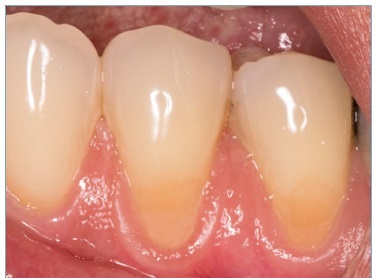

There were no dropouts in this study, so all patients were evaluated at baseline and at 6 months. Representative images of restorations are presented in Figures 1, 2, 3, 4, 5, and 6.

Figure 2 Photographs after 6 months of tooth 34’s restoration by the etch‑and‑rinse technique and tooth 45’s restoration by the self‑etch technique